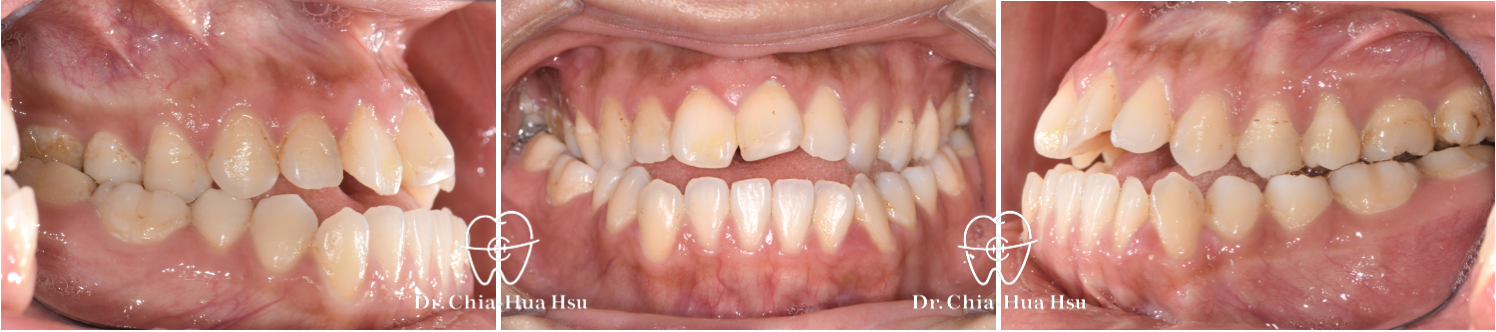

戽斗、前牙錯咬、開咬

成⼈矯正 | ⾦屬矯正 | 正顎⼿術

治療前

治療後